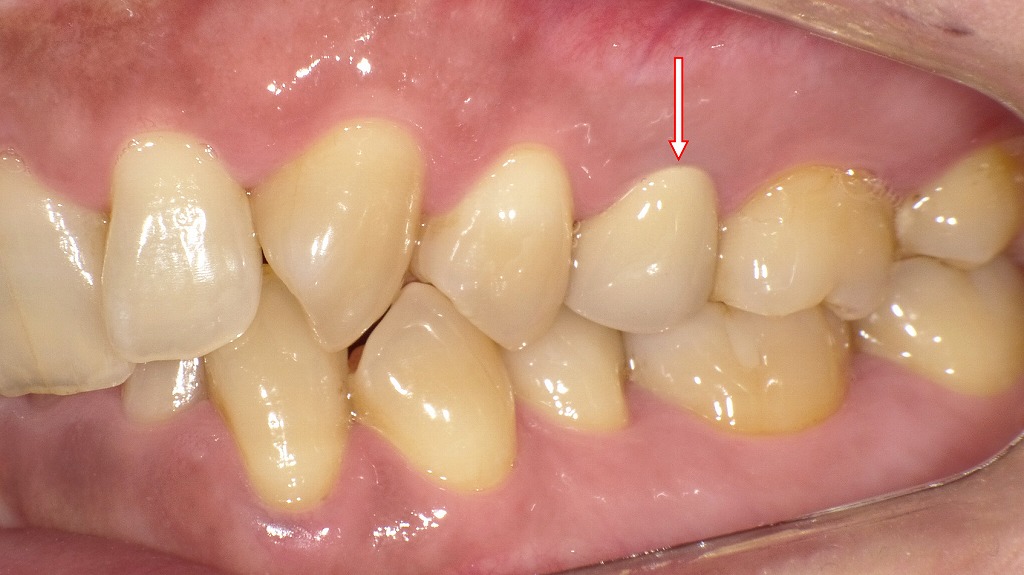

ジルコニアセラミッククラウンを装着した症例:側面観

この画像は、左上の第2小臼歯(通称「左上5番」)にジルコニアセラミッククラウンを装着した症例を示しています。以下に詳細を解説します。

🦷 対象歯(赤矢印部)

赤い矢印で示されている歯が左上5番(上顎第2小臼歯)です。

この歯にはジルコニアセラミック冠が装着されています。

💎 ジルコニアセラミックの特徴

- ジルコニア(内側):高強度で耐久性があり、金属アレルギーの心配がない。

- セラミック(外側):天然歯に近い透明感と色調を再現できる。

- 審美性と機能性を兼ね備え、奥歯でも長期間安定した使用が可能です。

👁️🗨️ 見た目の特徴

- 周囲の天然歯と色調・形態の調和がとれています。

- 歯頚部(歯ぐきとの境目)も自然で、歯肉の炎症や段差が見られません。

- 光の反射も自然で、人工歯特有の違和感が少ない仕上がりです。

⚙️ 機能面

- 咬合関係(上下の歯のかみ合わせ)も良好で、機能的な補綴物として適正に調整されています。

- 隣在歯との接触も自然で、**食片圧入(食べかすが挟まること)**が起きにくい設計です。

🩺 総評

この症例は、審美性・適合性・機能性のバランスがとれた良好な補綴治療例です。

ジルコニアセラミックは、特に金属を使いたくない方や自然な見た目を重視する方に適した選択肢です。